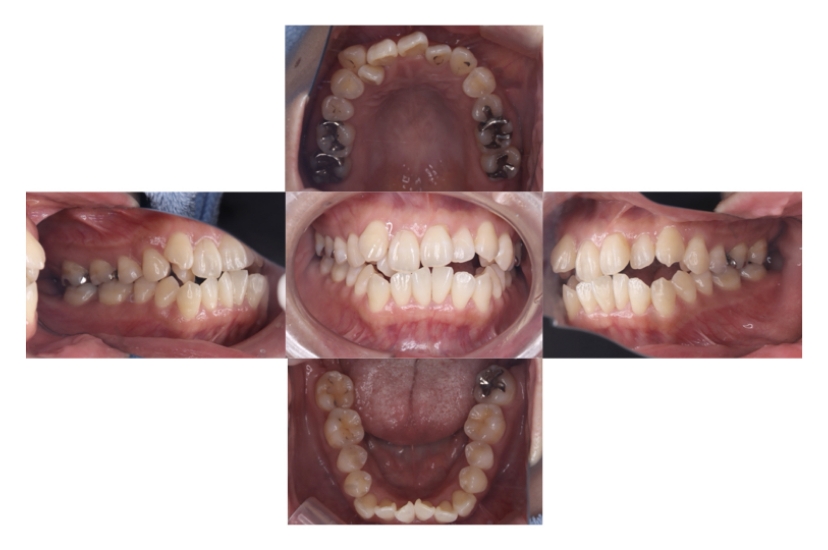

BEFORE

AFTER

上下顎前突、叢生

抜歯

ブラケット矯正

上下顎前突、叢生(上下出っ歯、上下の前歯のガタガタ)のケースです。

装置はラビアル(上下表側)で、上下顎の小臼歯を4本抜歯を行っています。抜歯したスペースを使って、上下の前歯の後方移動と叢生(ガタガタ)の改善を行っています。

主訴 前歯のガタガタと口元がでているのが気になる。

年齢・性別 30歳 女性

お住まいの地域 東京都大田区

治療方針 抜歯スペースを利用して上前歯の叢生(ガタガタ)と口元突出の改善

抜歯部位 上下顎左右第一小臼歯

使用装置 ラビアル(上下表側)、顎間ゴム

治療期間 1年11か月

治療回数 13回

リテーナー クリアリテーナー